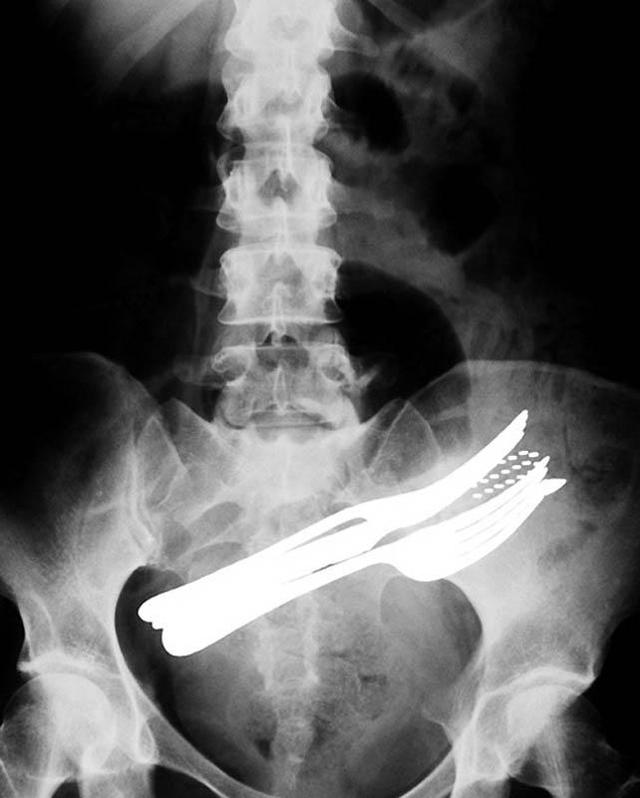

Живот пациента, который проглотил две вилки, шариковую ручку и зубную щетку.

Цветной снимок предметов, которые проглотил пациент, и которые застряли в его кишечнике, включая ложку и лезвие.